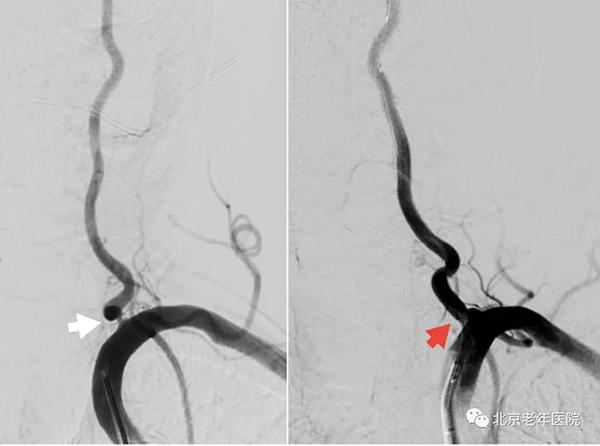

患者,男,71

岁,因“头晕2天,右侧肢体无力伴言语不利1天”入院。入院后确诊为脑干梗死。完善检查发现:左侧椎动脉重度狭窄。经充分的术前评估及术前讨论,认为患者脑干梗死诊断明确,同侧左侧椎动脉重度狭窄,考虑不稳定斑块脱落导致动脉-动脉栓塞,拟行脑血管造影+同期左侧椎动脉支架置入术。

术中造影显示:左侧椎动脉重度狭窄(白箭头),同期行左侧椎动脉支架置入术(红箭头)。手术进行了不到1小时,成功为患者植入一枚雷帕霉素药物洗脱支架,术后患者情况稳定,头晕症状缓解,出院时神经功能已完全恢复正常。